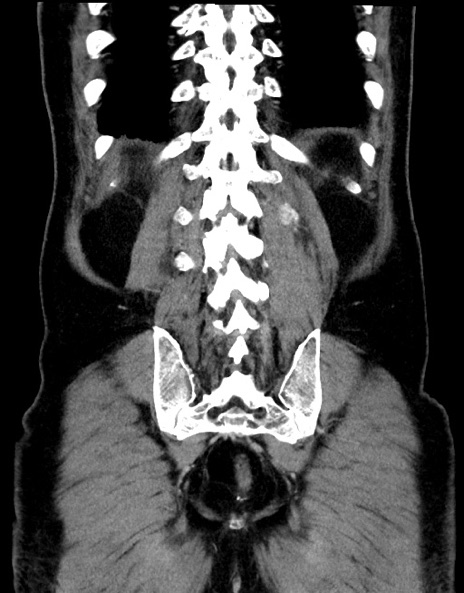

症例15(冠状断像)

【症例】70歳代男性

【主訴】腹痛

【現病歴】今朝から腹痛あり。全体的に痛い。特に左上の方。排ガスが今日はない。冷や汗が出る。

【既往歴】直腸癌術後

【身体所見】左側腹部〜上腹部に圧痛あり。腹膜刺激症状明らかなではない。軽度反跳痛。左下腹部に術後瘢痕あり。

【データ】WBC 7700、CRP 0.02